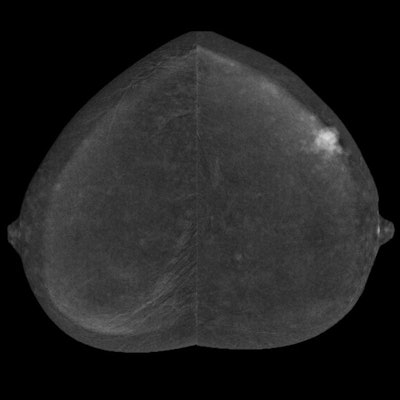

CMIST seeks to determine if contrast-enhanced spectral mammography (CESM) provides more accurate cancer detection compared with a combination of digital breast tomosynthesis (DBT) and whole-breast ultrasound in women with dense breasts.

Dense breasts mask breast cancer, making it harder to detect via mammography alone. As a result, many women with dense breasts are screened with DBT and breast ultrasound. But are there other methods that work just as well? CESM combines mammography and vascular-based screening methods that highlight unusual blood flow patterns. It could be a more efficient screening approach, according to the stakeholders. In fact, early studies of CESM in women with dense breasts show an increase in breast cancer detection rate by 70% to 80% compared with conventional mammography.